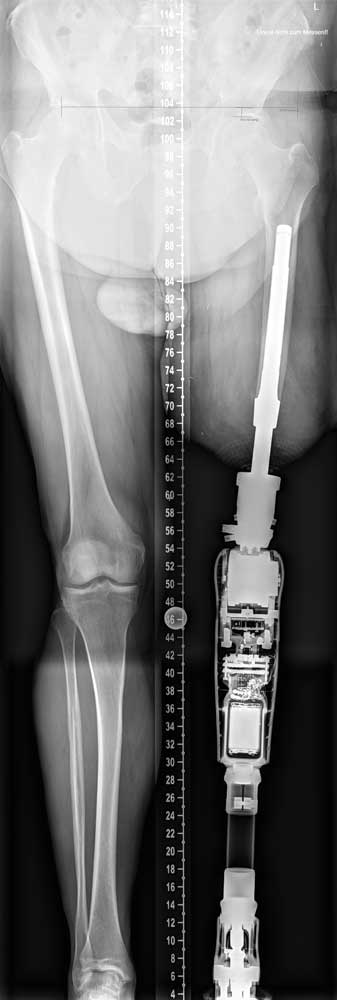

Um Funktionsvergleiche und Prothesennutzung vor und nach der Versorgung zu ermöglichen, werden zudem Daten per Fragebögen erhoben und klinische Testverfahren durchgeführt. Vor der ersten Operation wird zusammen mit dem Orthopädietechniker, dem Operateur und der ESKA Orthopaedic GmbH die Planung für die TOPS an referenzierten Röntgenaufnahmen vorgenommen (Abb. 9). Dabei fließen die Aufbauhöhe der geplanten Passteile, die Implantatgröße und die ossäre Struktur des Implantatlagers in die Planung ein. Anschließend wird bereits Kontakt zum Kostenträger gesucht, um das Vorgehen zu erläutern und Probleme im Versorgungsablauf zu vermeiden. Der weitere Verlauf:

Statischer Prothesenaufbau und Besonderheit des Brückenzylinders

Die Grundprinzipien des Prothesenaufbaus unterscheiden sich beim TOPS nicht von schaftgeführten Prothesen; die Passteile werden entsprechend den Herstellerinformationen aufgebaut. Die Besonderheit stellt die unmittelbare knöcherne Verbindung der Prothese dar. Aus diesem Grund sollten dem Orthopädietechniker beidseitige Ganzbeinaufnahmen zur Verfügung stehen. Hierdurch kann eine exakte Position der Längs- und Drehachsen der Knie- und Fußpassteile erreicht werden. Für die unmittelbare Verbindung der Exoprothese mit dem Brückenzylinder ist aus statischen Gründen ein Rückverlagerungsadapter notwendig. Die Größe des Modules ergibt sich aus den Anforderungen der Passteile sowie einer ggf. bestehenden Hüftbeugekontraktur. Insbesondere Letztere ändert sich innerhalb der ersten Wochen aber deutlich, sodass Anpassungen der Rückverlagerungsadapter notwendig sein können. Für den Fall ungewollter sehr hohe